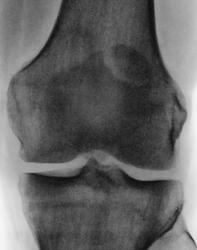

Несросшийся апофиз надколенника, деструкции не вижу

Такое развитие надколенника. Хотя может быть и травматический разрыв фиброзных сращений.

А, может быть просто пателла бипарцита?

Можно уточнение ? Край основной массы надколенника неровный, углы заострены и щель выглядит неравномерной -это обычная картина при удвоении надколенника ?

И мне это не понравилось. И по боковой - впечатление о смещении фрагмента.

Мужчина 39 лет, жалоб нет. Обратил внимание на разницу с другим коленным суставом (выпирает). Второй сустав на снимке без изменений. Травм утверждает, что не было.